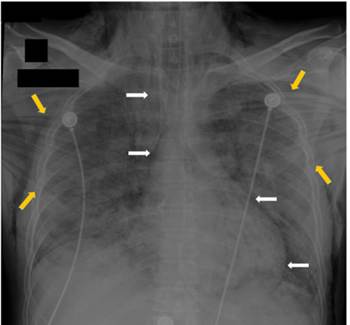

Paciente masculino de 44 años, referido de otra institución hospitalaria por deterioro de su condición respiratoria secundaria a COVID-19. Fue tratado inicialmente con ventilación mecánica no invasiva, pero desarrolló insuficiencia respiratoria severa por lo que requirió intubación orotraqueal de urgencia y ventilación mecánica invasiva. Al cabo de unas horas presentó un gran enfisema subcutáneo y neumomediastino confirmado mediante radiografía de tórax (Figura 1) y mediante tomografía computarizada de tórax, que informó además neumonía por COVID-19 severa, enfisema subcutáneo y neumomediastino masivo. Se identificó también una pequeña perforación traqueal distal de 5 mm localizada a la derecha de la parte membranosa (Figura 2). Presentó inestabilidad hemodinámica que requirió el inicio de vasopresores.